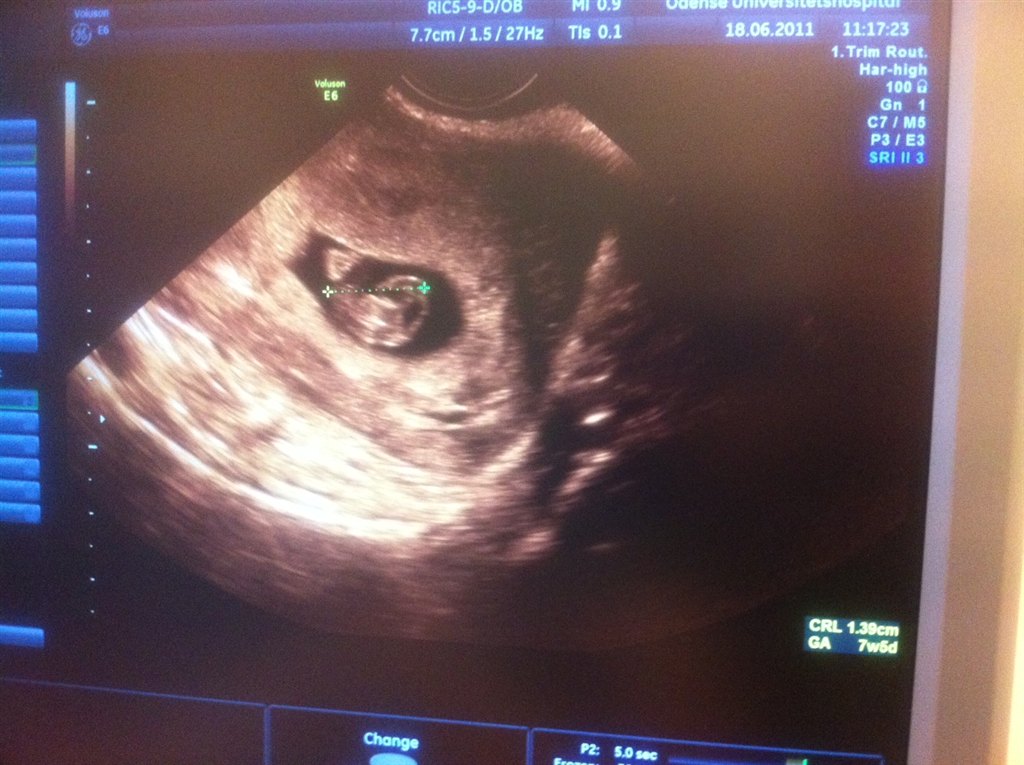

De målte den til ca. 7+6, jeg mener jeg er 8+1, men det er sådan deromkring

Og så lige et lille billede... hovedet er ved krydset til højre og numsen ved det andet kryds.